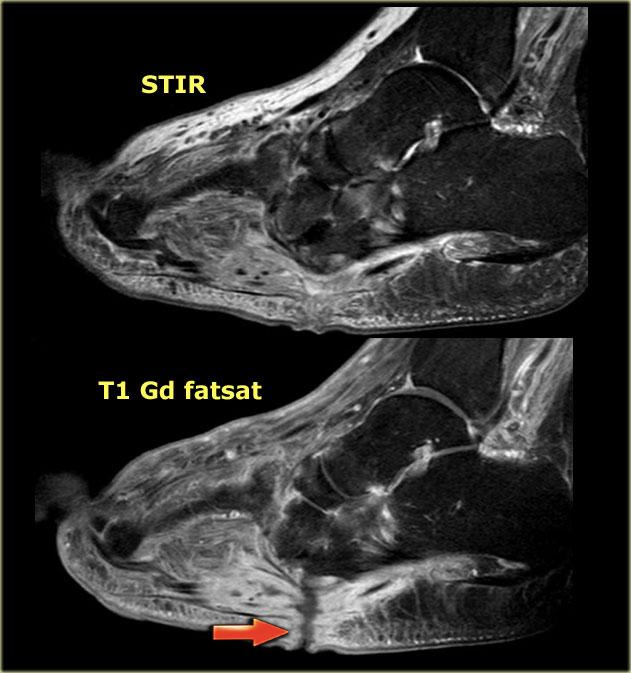

Charcot foot with rocker-bottom deformity and ulceration beneath the bony protuberance of the cuboid

Bên trái là hình ảnh điển hình của biến dạng bàn chân hình đế lắc do sụp vòm dọc.

Áp lực bất thường lên xương hộp đã dẫn đến loét.

STIR and T1W images in Charcot neuro-osteoarthropathy with a plantar ulcer (asterix) and osteomyelitis of the cuboid.

Ở bệnh nhân bị bệnh khớp xương thần kinh Charcot và bàn chân đế lắc, xương hộp là vị trí quan trọng của viêm tủy xương.

Nếu hình ảnh T1 tại vị trí đó cho thấy cường độ tín hiệu thấp kết hợp với khuyết hổng da, viêm tủy xương là cực kỳ có khả năng.

Hình ảnh STIR và T1 bên trái của bệnh nhân bị bệnh xương khớp thần kinh Charcot đang hoạt động với vết loét lòng bàn chân dọc theo chỗ lồi xương của xương hộp.

Có tín hiệu bất thường trong xương hộp cạnh vết loét, gợi ý viêm tủy xương.

Đây là các hình ảnh tăng cường tương phản có và không có bão hòa mỡ.

Sự tăng cường của xương hộp và các mô mềm lân cận trên hình ảnh sau tiêm thuốc tương phản, cùng với vết loét lòng bàn chân, làm cho viêm tủy xương rất có khả năng xảy ra.